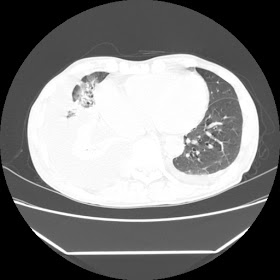

A 56 years old man with

HRCT done on summer season starting 2016